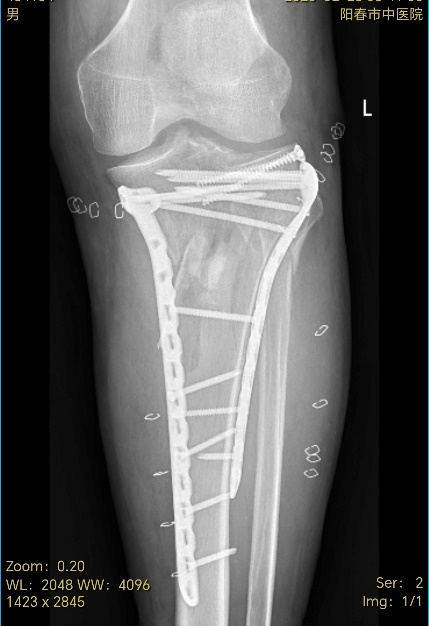

待时机成熟,创伤一科医疗团队迅速为李大爷实施了复杂胫骨平台微创内固定手术,术后又贯彻快速康复理念,通过多措并举的精心护理,极大地减轻了患者的痛苦,缩短了恢复周期。在医护人员的悉心照料下,李大爷的病情得到了显著改善,最终怀着感激之情顺利出院。

▼术后图像